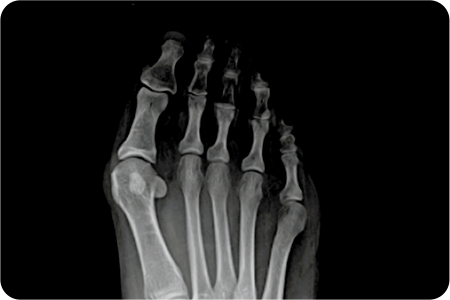

엄지발가락이 바깥쪽을 향해 휜 정도가 심각하고

통증으로 일상생활이 불가능할 경우,

변형 된 뼈를 깎아내고 각도를 교정해 줌으로써

근육, 인대등의 연부조직이 제자리를

찾을 수 있도록 하는 치료법

입니다.